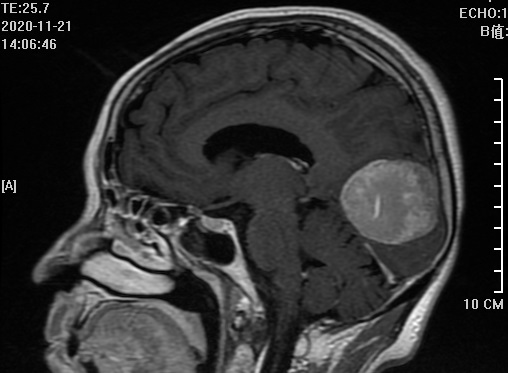

该病人在我院通过颅脑磁共振增强检查出左侧大脑镰旁占位性病变,来我院要求手术治疗,在完善相关术前检查时,患者的胸部CT结果却给我们带来诸多疑惑。

多学科协力成功切除镰旁脑膜瘤

近日,弋矶山医院专家刘策刚主任、赵心同主任和我院神经外科主任汪明义、ICU主任胡文涛、呼吸内科主任赵兴良、麻醉科主任张德文、感染科主任袁聂平等专家齐聚我院神经外科医师办公室,就一位左枕部镰旁占位(术后病理为:脑膜瘤

)

病人的病情展开多学科会诊及病历讨论。